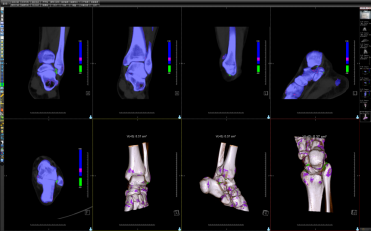

图⑥ 双源CT不同能级下扫描虚拟去钙技术对于骨髓水肿的判定。

图⑦ 双源CT不同能级下扫描后重建对痛风石检出。